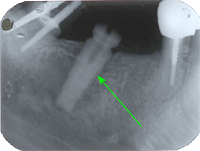

Ein 32 Jahre alter Mann kommt im November 1984 mit Zahnweh am unteren linken, zweithintersten Molaren (Backenzahn) in die Praxis. Das Röntgenbild von Abb. 1 zeigt insuffiziente Wurzelfüllungen bei allen drei Wurzelkanälen und an den Wurzelspitzen sogenannte Granulome, sichtbar als schwarze Flecken (grüne Pfeile in Abb. 1).

In Abb. 2 ist das Röntgenbild 22 Jahre nach korrekter Wurzelbehandlung mit dem nun überkronten Zahn zu sehen. Der Knochen um die Wurzelspitzen ist entzündungsfrei gesund.